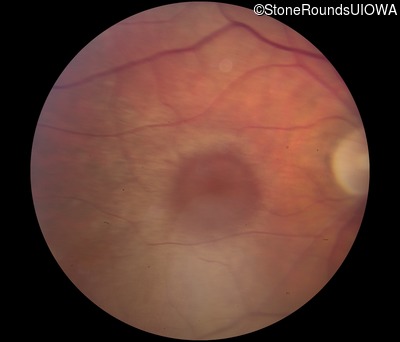

Visit at age: 39 years

Fundus Photography - Right - 20/50 +2 sc

Exemplar